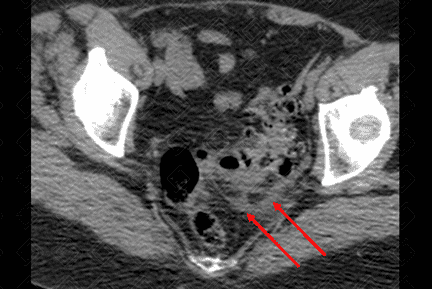

Texto alternativo para a imagem Figura 2. Créditos: Dra. Elazir Mota - Rio de Janeiro/RJ

Descrição das figuras 1 e 2: Tomografia computadorizada do abdome. Presença de alguns divertículos colônicos (figura 1 - asterisco), mais evidentes no sigmoide, no qual observa-se densificação dos planos adiposos e lâmina líquida de permeio (figura 2 - setas vermelhas). Achados compatíveis com diverticulite aguda não complicada do sigmoide.